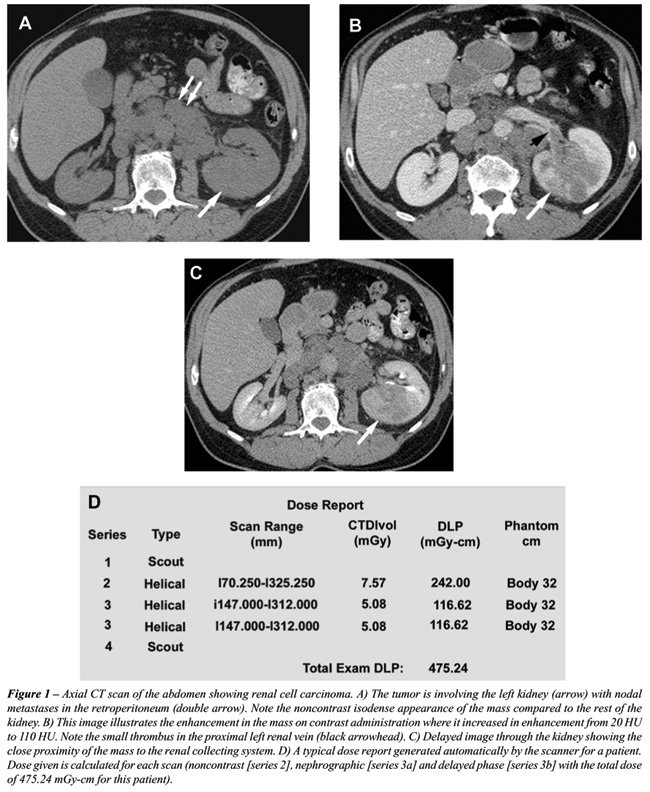

A precontrast phase provides a baseline from which to measure the enhancement within the lesion after the administration of intravenous contrast material. Calcifications are also seen in 30% of cases of RCC. The enhancement characteristic is important in distinguishing hyperdense cysts from solid tumors (Figures-1A and 1B). Because most renal cell carcinomas have a rich vascular supply, they enhance significantly after administration of intravascular contrast material. Enhancement values of more than 15-20 HU are considered suspicious for malignancy (8); more variation in enhancement is found with small masses due to the dense opacification of adjacent normal parenchyma.

Generally, dual phase imaging with a nephrographic phase and a delayed phase is used for evaluating suspected renal neoplasms and depicting perinephric extension and vascular anatomy. For dual phase imaging, 150 ml of non-ionic lower osmolality contrast media (320 mg ml-1) is injected at 3 cc/sec and images are acquired following delays of approximately 90 seconds and 6 minutes for the nephrographic and pyelographic phases, respectively. In some institutions, an initial scan is also performed in the corticomedullary phase. In the corticomedullary phase, the contrast material is primarily in the cortical capillaries, peritubular spaces, and cortical tubular lamina and has not yet filtered through the more distal renal tubules (9). In the nephrographic phase, the contrast material filters through the glomeruli into the loops of Henle and collecting tubules (9). The renal parenchyma enhances homogenously during this phase, due to tubular accumulation. Renal tumors enhance less than the surrounding parenchyma in this phase, because they lack normal glomerular-tubular function and hence this phase is most valuable for detecting renal masses and characterizing indeterminate lesions (10). The contrast reaches the collecting system during the delayed or the excretory phase and, as a result, the attenuation of the nephrogram progressively decreases (Figure-1C). Macari & Bosniak (11) have suggested that measurement of the washout of contrast material from a lesion at 15 minutes allows differentiation between hyperdense cysts and renal neoplasms. In their study, there was no change in the attenuation of high-density cysts between the initial contrast-enhanced CT scan and the 15-minute-delayed images. In comparison, all lesions that proved to be neoplasms at surgery or follow-up studies showed a decrease in attenuation or “de-enhancement” of at least 15 HU at delayed CT, which was attributed to the washout of contrast material from the vascular bed of the tumor (11).

Contiguous thin sections are obtained using protocols dependent on machine manufacturer to enable overlapping reconstruction. At our institution, multiphase CT scans are obtained on GE Lightspeed VCTTM 64 slice scanner at 0.625 mm thickness at a pitch of 1.375:1. These slices are reconstructed at 2.5 mm thickness in the axial plane and coronal reformats are obtained at 5 mm intervals. Sagittal reformats and 3D reconstruction are performed on a case specific basis. Cardiac gated studies are performed for patients with IVC extension (see Figure-4). Multi-phase CT of the abdomen is performed from top of the liver to 1 cm below the lowest kidney. A 15 minute scanogram is performed at the end of the exam to assess the ureters. The protocol used at our institution is illustrated in Table-1.

TECHNICAL CONSIDERATIONS

Standard oral contrast media for pre-operative assessment of renal neoplasm and vasculature is unnecessary and may, in fact, obscure intravascular contrast. The radiation dose in our CT scanners is regulated using the Smart mATM feature, in which the mAs used is regulated according to the amount of tissue (bone/soft tissue) that has to be traversed in x, y and z axes. For example, the mAs used in the mid-abdomen is less than the mAs used in the pelvis due to the bony structures in the pelvis. The radiation dose given also depends on the patient’s size with more dose required for larger patients and less for smaller patients. This is regulated according to the body thickness as illustrated in Table-2. Maximum mAs to be used can also be set in this Auto-mATM feature. Figure-1D illustrates the average dose generated during each scan and the total dose report.